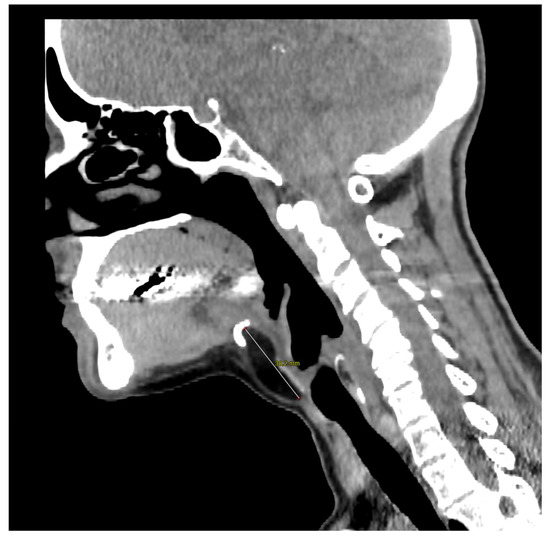

Figure 1.

A computed tomography of the neck on the axial plane demonstrating a 10 × 17 × 38 mm (AP × LL × CC) lesion and its relationships with the anterior border of the thyroid cartilage of the larynx. The anatomical subsite pinpoints to a possible persistence of the thyroglossal duct (TGD). This represents an embryological remnant during the migration of the endodermal thyroid diverticulum, and it may extend from the foramen cecum of the base of the tongue to the suprasternal notch [1,2,3]. TGD can variably persist in up to 7% of the adult human population, and its incomplete obliteration (usually by the tenth week of gestation) leads to the creation of the pyramidal lobe of the thyroid gland as well as many other neck disorders, including lingual thyroiditis and TGD cyst [4]. The latter in particular is the most frequent congenital central neck mass and it usually presents around 30–40 years of age as an infected cyst (more rarely as a fistula or a sinus), causing neck discomfort and dysphagia [5,6]. Their treatment usually consists of open surgical excision along with the central portion of the hyoid bone’s body and a core of tongue musculature, as described in 1920 by Walter E. Sistrunk from the Mayo Clinic [7]. The differential diagnosis of TGD cysts and midline masses is vast and it includes, among others, dermoid and epidermoid cysts, cystic nodal metastases of papillary thyroid carcinoma, lymphangiomas, lymphomas, ectopic thyroid adenomas, or lipomas [4,8].